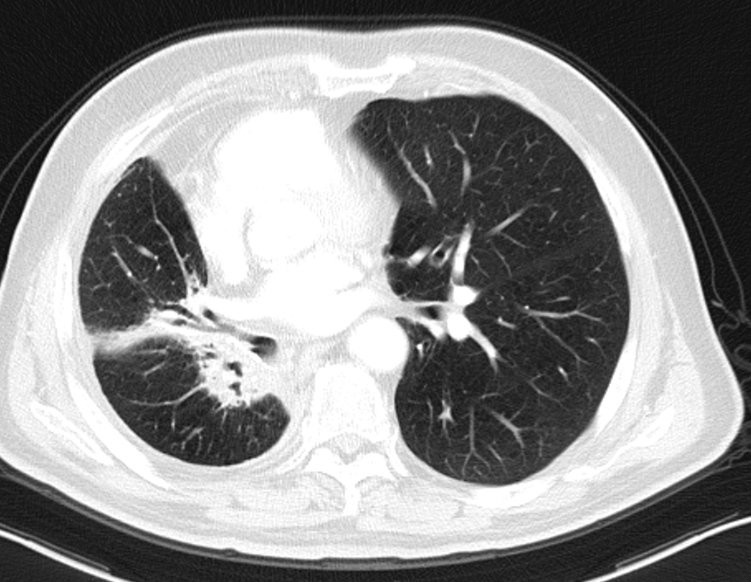

(2018年10月9日胸部CT见右肺中叶放疗后改变)

(2022年5月27日胸部CT提示病灶稳定)